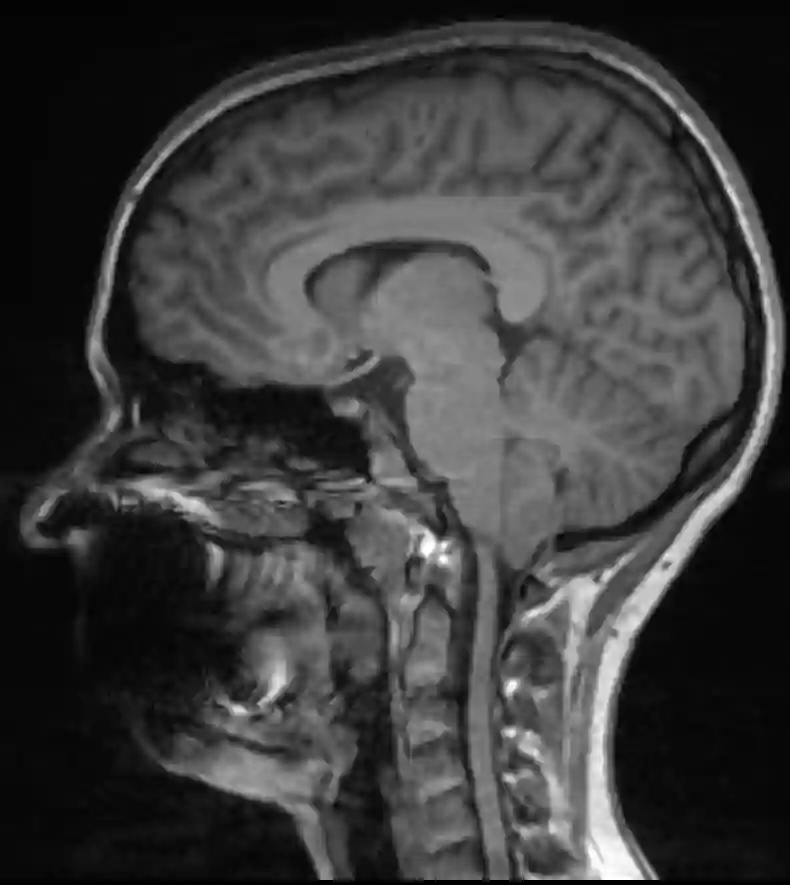

Chiari I Malformation im MRI

Sagittales T1 MRI Bild eines Patienten mit einer Chiari 1 Malformation.